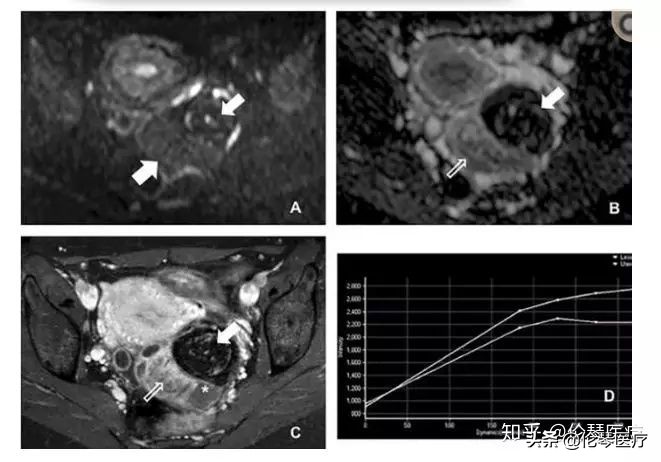

简单地说,磁共振通过功能成像可以了解组织成分的功能状态。扩散加权成像(DWI)可以反映肿瘤组织里水分子的扩散状况。一般来说,恶性肿瘤因为细胞增殖快,细胞里面的水分子弥散速度降低,水分子运动受限,在DWI上表现为高信号。而良性肿瘤,由于组织松散,水分子在细胞之间很容易运动,在DWI上呈低信号。这样就很容易分辨出绝大部分肿瘤到底是良性还是恶性。

如图所示,患者左侧卵巢上有一个非常实性的肿瘤,在DWI上信号非常高,且在增强扫描中也有中度的强化,说明肿瘤细胞很致密,水分子在细胞间不容易运动,可以诊断为恶性肿瘤。实际上,该病例是一个输卵管癌。